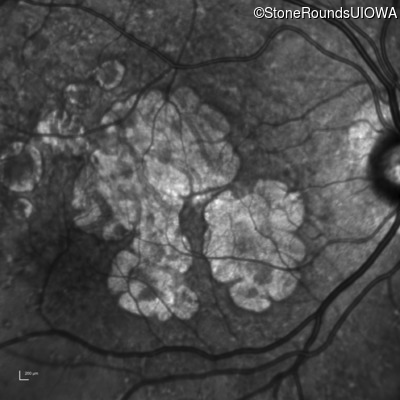

AR Stargardt Disease (IIA)

Age at visit: 59 years

This 59 year old man has noticed some blank spots near the center of his vision over the last 2 years.

AR Stargardt Disease ABCA4 Leu2027Phe CTC>TTC IVS30+1321 A>G AR